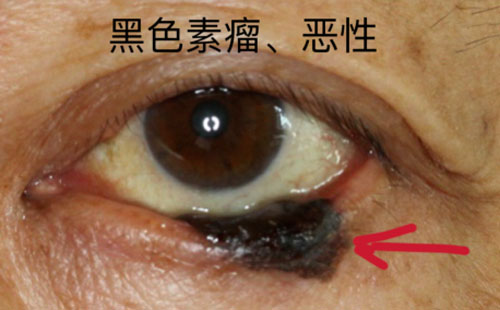

眼腫瘤包括眼瞼、結膜、眼內、淚器、眼眶腫瘤。眼瞼惡性腫瘤常見基底細胞癌,瞼板腺癌、鱗狀細胞癌和黑色素瘤,良性腫瘤常見于色素痣和血管瘤;眼眶腫瘤包括淋巴瘤、腺樣囊性癌、海綿狀血管瘤、神經鞘瘤、神經纖維瘤等;眼內腫瘤以惡性多見,主要見于視網膜母細胞瘤、脈絡膜黑色素瘤、脈絡膜轉移癌等。

對于眼瞼的腫瘤,會充分考慮到顏面部的美容需要,在確保清除病變的同時,完成整形修復。眼瞼腫瘤表現多種多樣,良性病變多生長緩慢,邊界清楚。但是如腫塊突然增長加速,有破潰、出血,疼痛,色素性腫塊有色素播散現象時,您必須引起高度重視。絕大部分惡性腫瘤都發生在中老年人,而年輕人的眼瞼腫塊多是炎癥變化。

如果您到醫院就診,醫生借助放大儀器可以更清楚地觀察病變。部分惡性病變的早期難以完全憑臨床經驗確診,醫生會建議您手術活檢,通過病理來確診。若是惡性,手術切除治療是首選療法,切除的范圍取決于腫塊的大小、位置、深度。皮片移植或皮瓣轉移、游離帶結膜臉板移植、口唇或聘粘膜移植等方法可以修復腫瘤切除后遺留的巨大缺損。眼瞼“寸土寸金”,即使腫塊只相差1毫米,手術也會由簡變繁,所以早治療是重中之重。